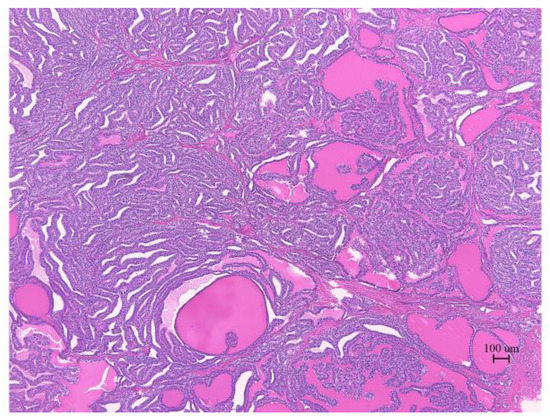

The pathological analysis of the resected tumor indicated that the histological type was a highly differentiated follicular carcinoma (Figure 3). No findings of papillary carcinoma, such as psammoma body, intranuclear cytoplasmic inclusion, ground glass nuclei, or nuclear groove, were observed. Similar histology was observed on the posterior wall of the uterus, omentum, and mesentery. This case was diagnosed as Stage IIIC by the 2014 International Federation of Gynecology and Obstetrics (FIGO).

Figure 3.

Micrograph (H&E staining) of the malignant struma ovarii. The thyroid follicular structure was the main component.